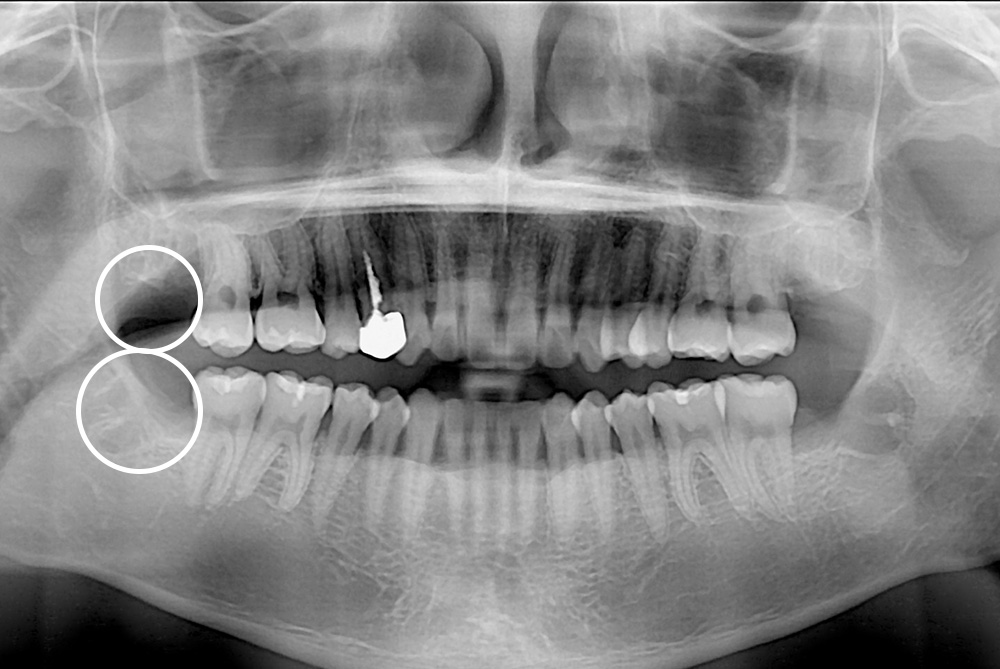

[사랑니] 매복 사랑니 발치

치료전 : 2016-03-15

세종치과는 구강악안면외과학 박사이신 원장님이 발치하는 치과입니다.